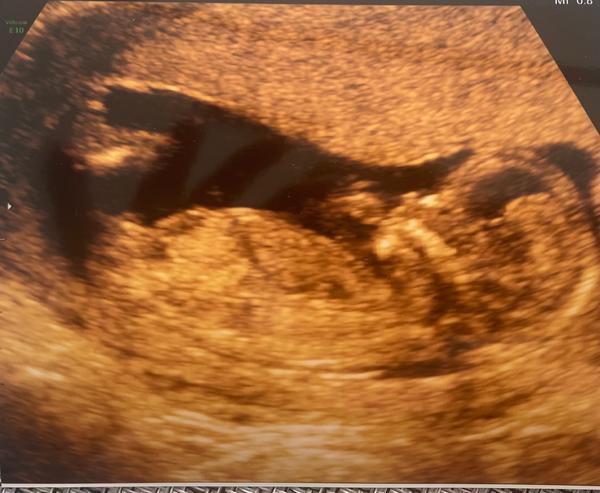

Rozlišení pohlaví miminka na prvním screeningu: Jak na to?

Ahoj, pomohl by mi prosím někdo rozlousknout pohlaví u miminka? My se zapomněli zeptat a prý už to na tom prvním screeningu je poznat 🫣🤦♀️🤦♀️🤦♀️ Děkuji moc ♥️

Tak z tehle fotky to fakt nejde videt. To by to mimko muselo byt nejak natocene. My treba meli holku a ta se natocila dupou k nam a slo videt kavove zrno. Takze jasna holcicka. Ale tady? To muze byt fakt typovacka

Jestli to co tam je trosku vidět je pohlavní hrbolek, tak by se dalo odhadnout. Mrkni se jak vypadá pohlavní hrbolek v tomto týdnu u kluků a holek. Poznává se to podle toho jestli je s páteří rovnoběžné nebo je lehce nahoru.

Jestli je to pohlavní hrbolek, tak to vypadá na holčičku.